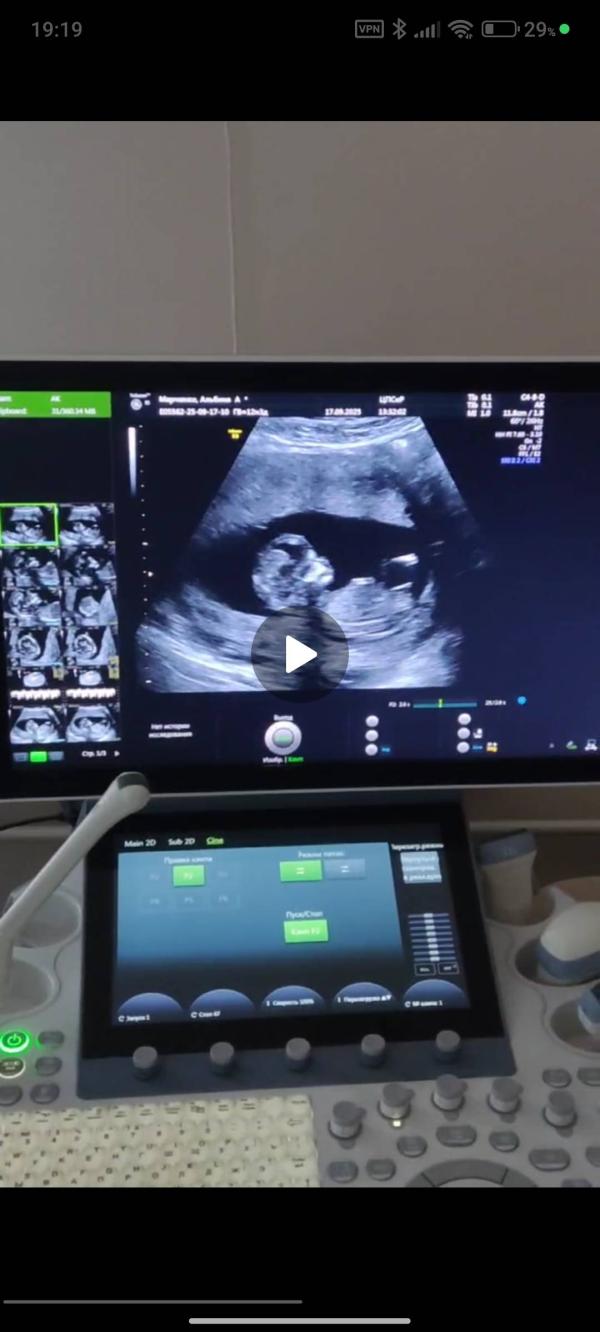

Сегодня прошла первый скрининг по омс. Завтра пойду на УЗИ к Тё Сергею Александровичу, главный вопрос к нему можно ли увидеть какие то проблемы с плацентой на узи, потому что просто "все хорошо, гуляй" меня не устраивает. Терапия есть, в ближайшее время думаю обновить анализы по афс, анф (у меня только анф 160 положительный)

По скринингу вижу девочку своим профи мамским взглядом. Муж скромно надеется уже 2 беременности на мальчика, но это его проблемы 😄

Думаю , Тё Вам завтра скажет, правы Вы или у мужа праздник будет))

У меня тоже был бугорок вниз, все здесь писали девочка, в итоге мальчик))

Тоже девочку вижу 🥰мне кажется я уже спец по этим бугоркам😂